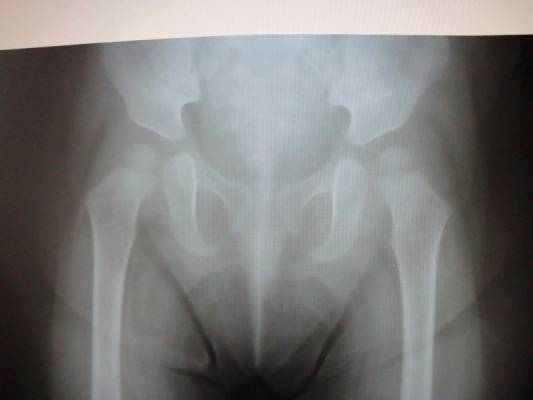

Альбом ДИСПЛАЗИЯ ТАЗОБЕДРЕННЫХ СУСТАВОВ ?. Фото " уточнение диагноза "Дисплазия тазобедренных суставов" ребенку 1 год." 34.7 k (800x600) DSC04877.JPG

уточнение диагноза "Дисплазия тазобедренных суставов" ребенку 1 год.